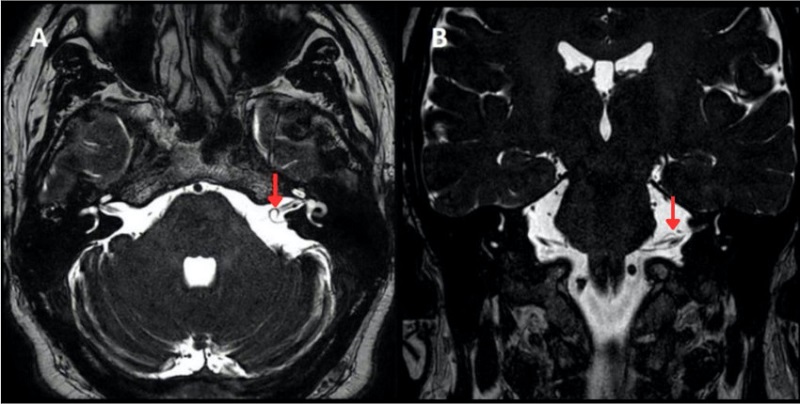

Se utilizó el sistema Chavda para definir la extensión del loop vascular (Fig. 3). La clasificación se compone por tres tipos: el tipo I es un loop vascular situado en el ángulo pontocerebeloso, que no ingresa al CAI

(Fig. 4); el tipo II loop vascular ingresa, pero sin extensión mayor del 50% de la longitud del CAI (Fig. 5), y el tipo III loop vascular con extensión mayor del 50% de la longitud del CAI (Fig. 6)8.

Según la clasificación anatómica Chavda (Fig. 3), el tipo de loop vascular más frecuente es el tipo I de oído (derecho: 52,6%; izquierdo: 33,3% y bilateral: 14,1%) (Fig. 4 A y B), seguido del tipo II de oído (derecho: 31,3%; izquierdo: 37,5% y bilateral: 31,3%) (Fig. 5 A y B) y el tipo III de oído (derecho: 50,0%; izquierdo: 25,0% y bilateral: 25,0%) (Fig. 6 A y B) (Fig. 9).